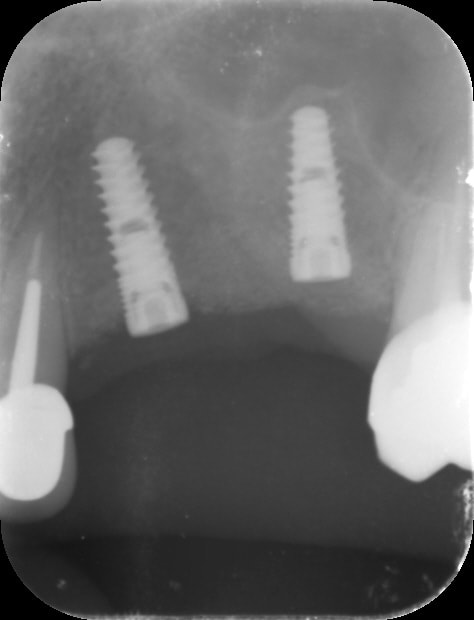

par contre je fais pas mal de radios, exemple spreaders trop près de la racine donc changement d'axe (d'où l’intérêt de l'expansion)

est ce que sur la pano que je poste ces Implants postérieurs sont dans l'axe ? 😊 Est ce que ça pose problème ? J'ai pas l'impression 😊😊😊. Alors tu vas peut être me dire que c'est différent : on est dans des divergences d'axe dans le sens mesio-distal et non vestibulo lingual. Mais Ils ne sont pas tout à fait dans l'axe des dents on dirait, non ? Alors si on extrapole est ce que la ptite divergence d'axe dans un cas comme Le mien pose problème alors qu'au départ il n'y avait quasi pas d'os , ni en largeur ni En hauteur...